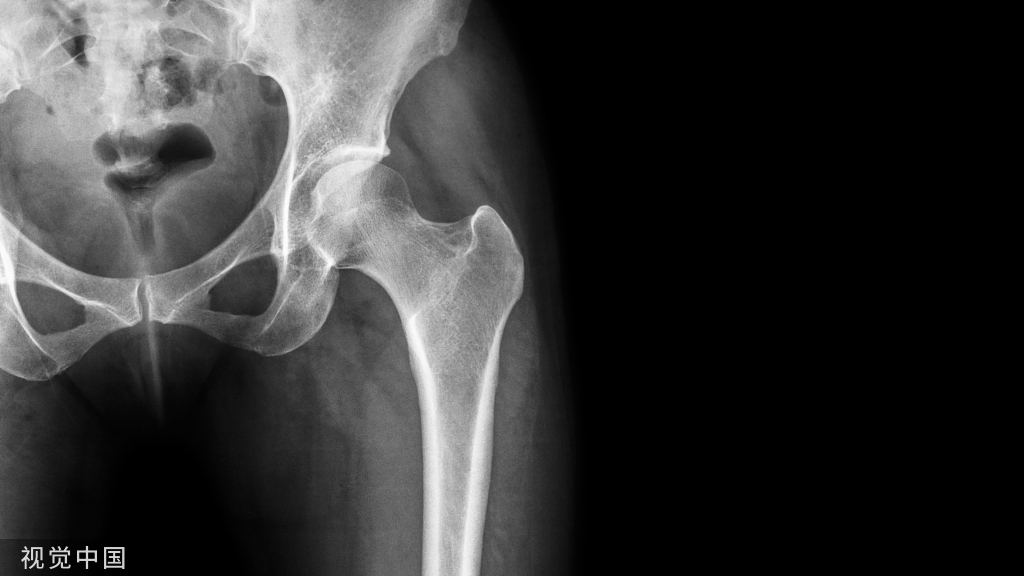

- 术中如需用牵引床的体位护理:

- 需妥善固定手术床、牵引床、患者;

- 用约束带将患者上身固定在手术床上,健侧上肢用束臂带固定于搁手架上,患侧上肢置于头部或加软垫包裹置于胸前;

- 会阴处加棉垫保护阴囊以免牵引过程中阴囊受压;

- 双下肢用治疗巾包裹固定在牵引床上,用约束带固定;

- 术中若需在髂前上棘处取骨植骨,可在髋部垫一软垫,将患处抬高15°~20°便于医生取骨。